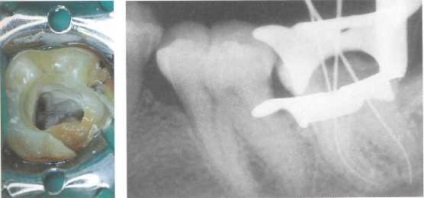

Ábra. 44. feldolgozása a gyökér-O csatornákat.

Miután radiológiai op-meghatározása gyökér hossza ka-fogás mechanikusan működött ob-up válaszok csúcsi az ólban. Nem megfelelő kezelése a gyökércsatorna vezet CO-tároló nem csak nskrotizirovannoy cellulóz, hanem a szövet-képzett mumifi kapcsolatos parafarmaldegidom. Ez a mo-Jette sprovotsi-MENT-alapú közösségek Immunol reakció lassult-bizonyos típusú. Balra: A gyökérkezelés obra--

Botha és kibővítették.